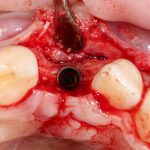

Рекомендации по установке имплантов. Для всех. Часть V.